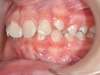

Cas 4 : Description

Chevauchement sévère. Traitement multibague sans extraction.

Avant

Après